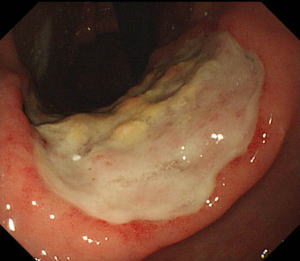

| 【胃ESD】 |

治療の1週間後の内視鏡所見。出血もなく潰瘍は治癒傾向で、無事退院されました。 |